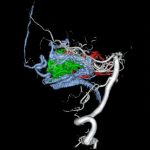

手術中

手術写真

手術前

手術後